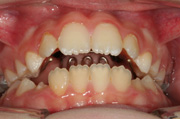

.... griglia linguale ( solo 4 mesi) e successivamente con Barra palatale in intrusione (discostata dal palato),in contemporanea al dispositivo elastodontico. Sono state associate sedute di terapia miofunzionale logopedica. Il caso e' ancora sotto controllo ma la durata di trattamento effettiva e' stata di anni 2!.